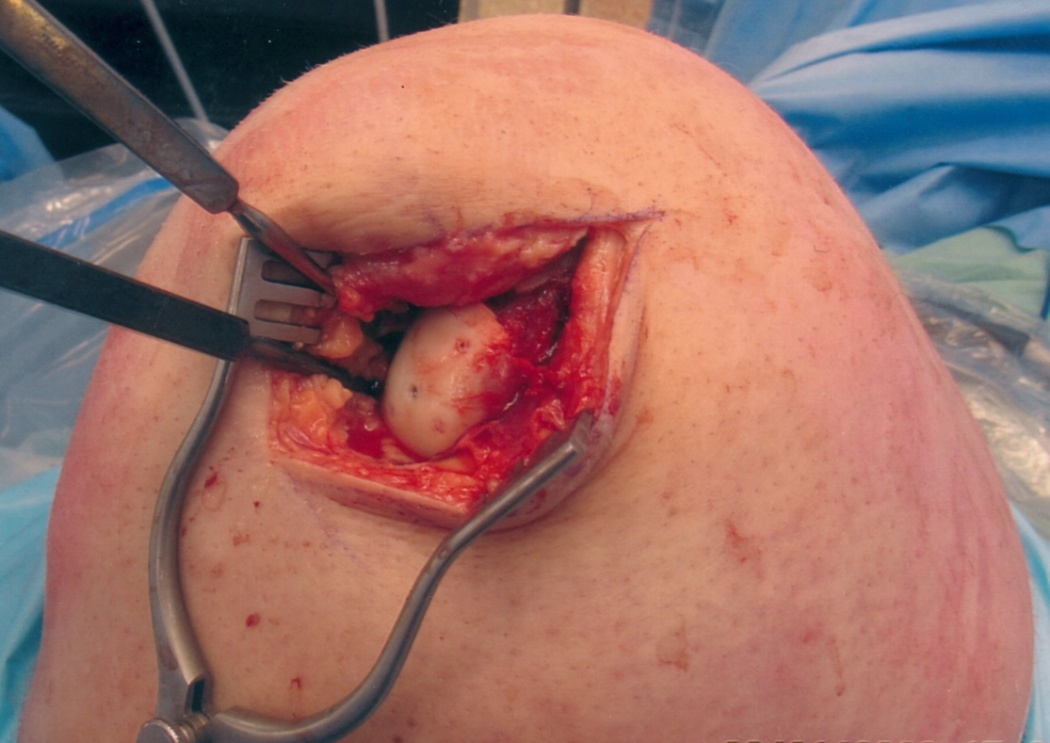

Patella dislocation was treated conservatively. The patient was taken to operating room for fixation of the OCF. The OCF was hinged open and irrigated with saline (Figure 7). It was stabilized with 1.2 mm K-wire. Fixation was achieved by using a 3x22mm Bio-compression screw (Arthrex) in the center followed by four 1.3x18mm chondral darts (Arthrex) around it (Figure 8).

Figure 7 Intra-operative picture showing lateral femoral condylar osteochondral fracture.